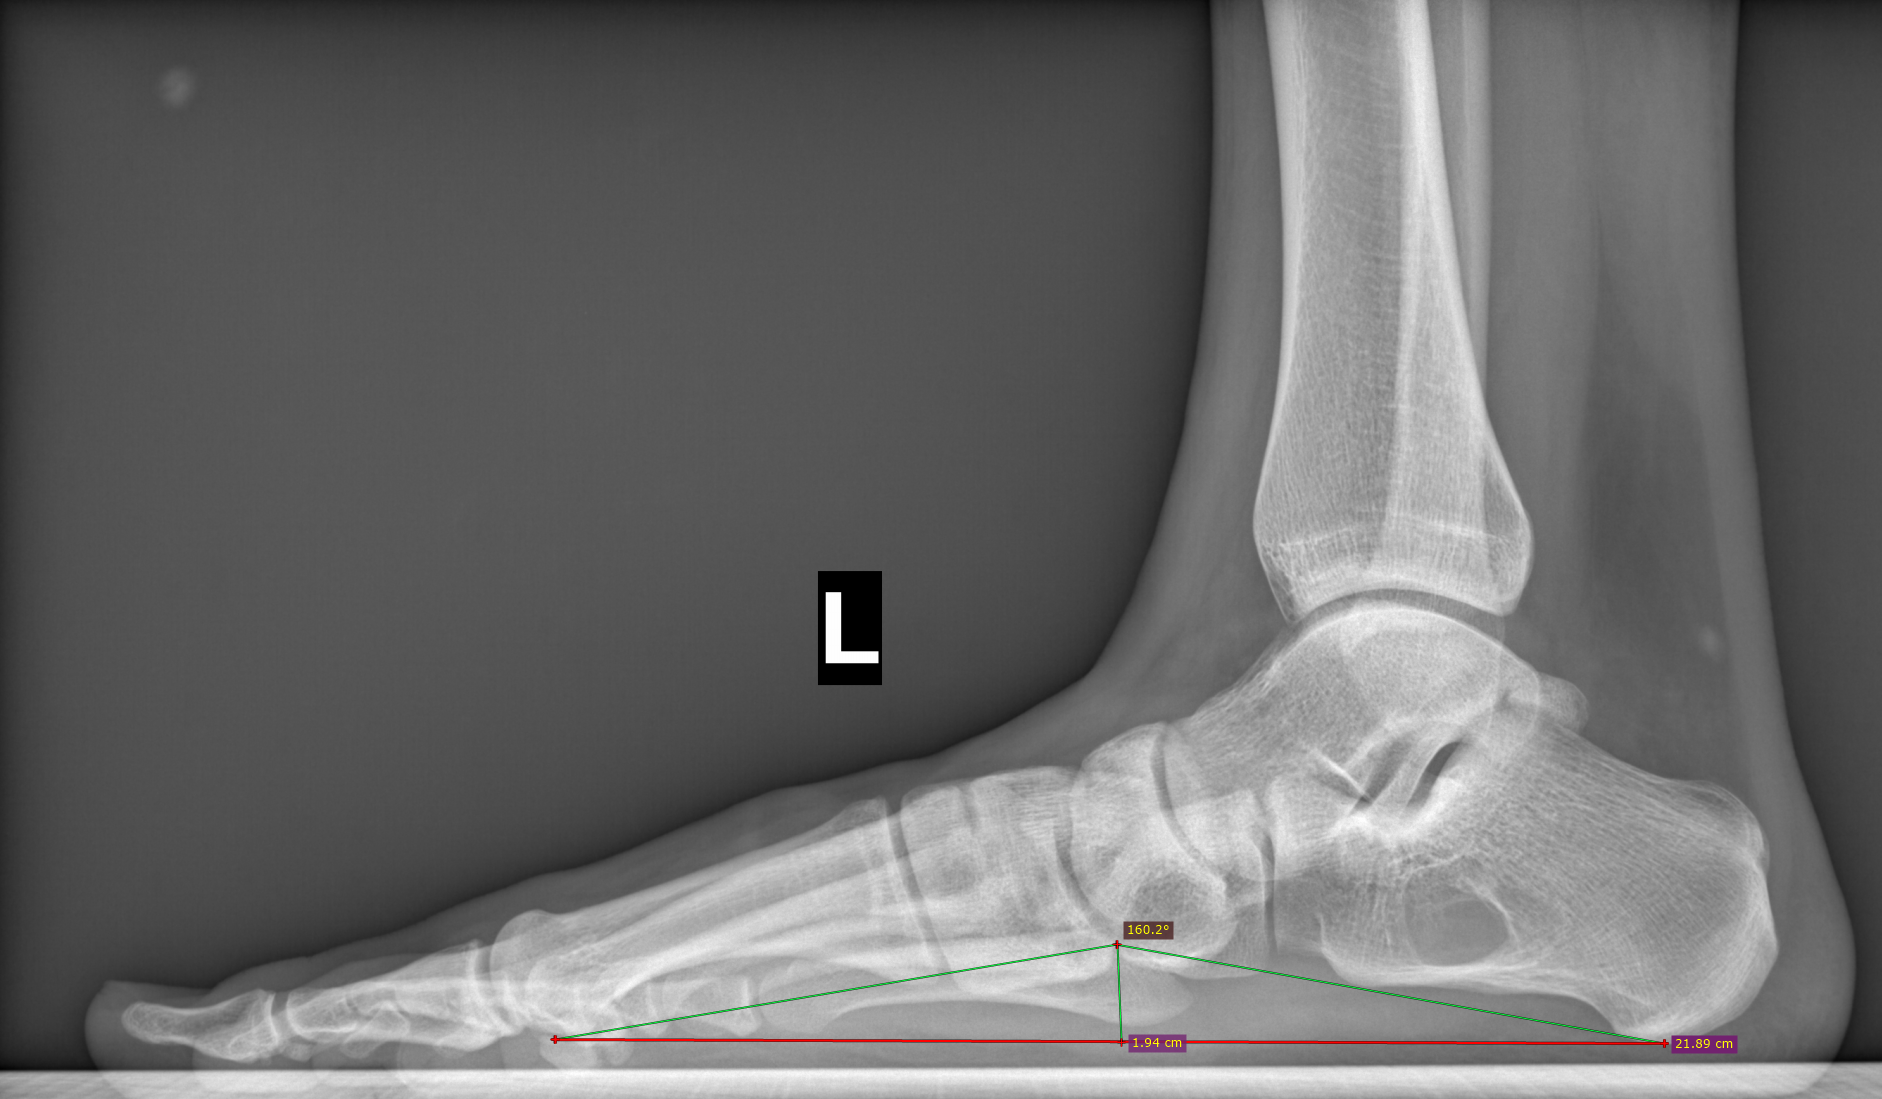

Угол продольного свода левой стопы 160 град., высота 19 мм, соответствует продольному плоскостопию 3 ст. левой стопы.